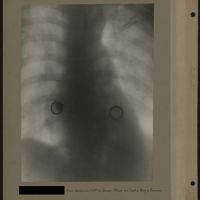

0058 - Page 54 - [Radiographie du thorax]0058 - Page 54 - [Radiographie du thorax]